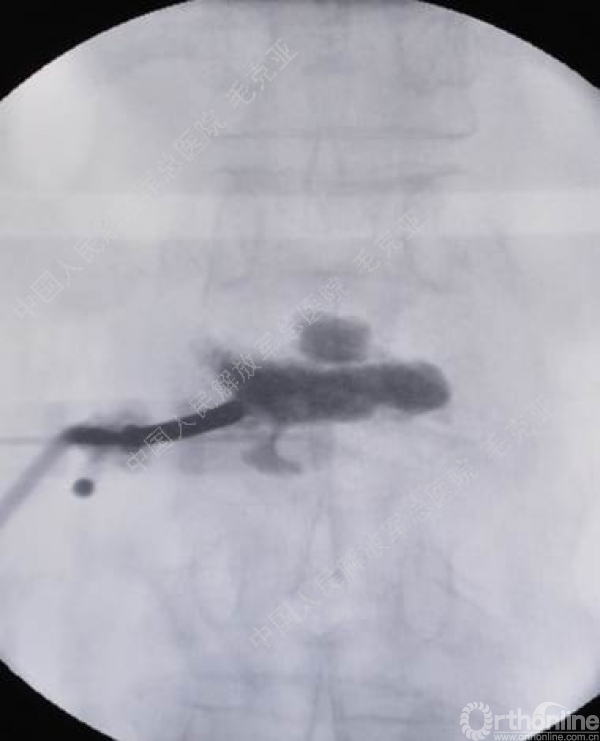

导语:随着社会老龄化的不断加速,骨质疏松性椎体压缩骨折作为一种普遍存在的老年骨科疾病已经成为现今骨科界的一个热点话题。传统的保守疗法治疗效果不佳,而现有的椎体增强技术又具有多种风险和缺陷。针对这种现状,中国人民解放军总医院毛克亚教授提供了一种新的解决方法。